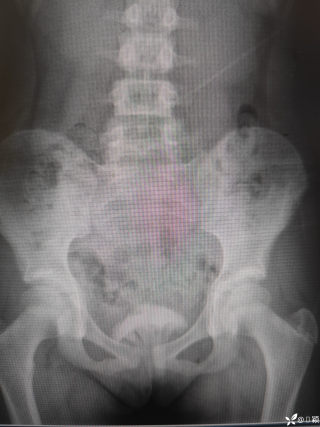

灼见|如果是你,如何处置山东男孩(多器官切除病例)

文/西地兰 特别声明:所有观点仅代表个人言论 特别声明:与当事双方均无利益相关 山东男孩,目前全网沸沸扬扬,看过一些观点,直言不讳地说,大多偏颇。要么一股脑地指责医方的全责,甚至有说千万别在县医院看病。要么又为医方无休止的遮羞,认为这样的手术在县医院做下来已经非常了不起。而我想到的是,以后面临类似的病例,我们怎么办?那么我们不如来一次专业的病案讨论。既然是事后讨论,难免有事后诸葛亮的感觉,但是假如下一次,同行们遭遇这样的病例,如何处置?这是医疗行业所面临的问题。希望我整理的这些思路和相关病例,对同行们有所帮助!就目前的资讯外界不足以判断是否需要急诊,如果需要急诊,那么只能根据术中所见进行处理,

目前知道的消息,第一,术前发现一个血肿,然后做增强CT发现一个占位,没说血肿与肿瘤的关系,术后病理没有描述肿瘤出现破裂出血,大概率就一个小血肿,我就不明白当地主任凭哪个指针去给这小孩开急诊刀的?哪个指南告诉他需要急诊开?第二,诊断不明确他想的不是进一步检查,一边观察一边进一步查,他反而选择腹腔镜探查,这个探查的指针在哪?第三,腹腔一个血肿,没有活动性出血,没有血压心率出现问题,为什么要开腹进去碰它?不能等血肿吸收再明确肿瘤性质吗?第四,1点进腹,3点病理结果出来,按这个时间还算顺利,应该还没出事,孩子还算平稳,病理是低度恶性,切了就治愈,他一年能开几台这手术,就敢继续做,拿孩子练手。第五,后面

2023年10月26日,来自山东菏泽市成武县的小烨和他家人的命运被彻底改变了。这个原本阳光、可爱的小男孩在一次意外被撞击后,在医院检查出了腹腔内存在肿瘤,并在手术中被切除了包括十二指肠、胰腺、大部分胃和小肠等多个器官。此后便无法再像正常人一样吃饭、喝水,活着要靠长期静脉注射营养液。一份2024年12月由第三方机构出具的司法鉴定意见书显示,当时给小烨做手术的成武县人民医院在该医疗行为中存在过错,与小烨的损害后果之间存在因果关系,建议医疗过错在损害后果中的原因力大小为同等原因。此外,另一份由成武县卫生健康局在2025年9月28日发出的书面答复中显示,成武县人民医院存在24小时内未完成病历;手术知情